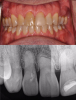

Figure 14 through Figure 18 show a partially dentate patient for whom a fully digital workflow was utilized. This 47-year-old male presented with root blunting and mobility of teeth Nos. 7, 8, and 9 (Figure 14). A thermoplastic clip was attached during the CBCT, and an intraoral scan was taken and superimposed on the CBCT. The case was then planned in the navigation planning software (Figure 15). Once the teeth were extracted, intraoral scanning was performed. The intraoral scan was imported into lab software (Figure 16), and a PMMA milled screw-retained prosthesis was fabricated. The prosthesis was placed the next morning (Figure 17). Two months later, a new intraoral scan was taken to capture the mature soft tissue, and the final milled titanium abutment and restoration were delivered (Figure 18).

Fig 14. Preoperative view of a partially dentate case. Patient with root blunting and grade 3 mobility.

Figure 14